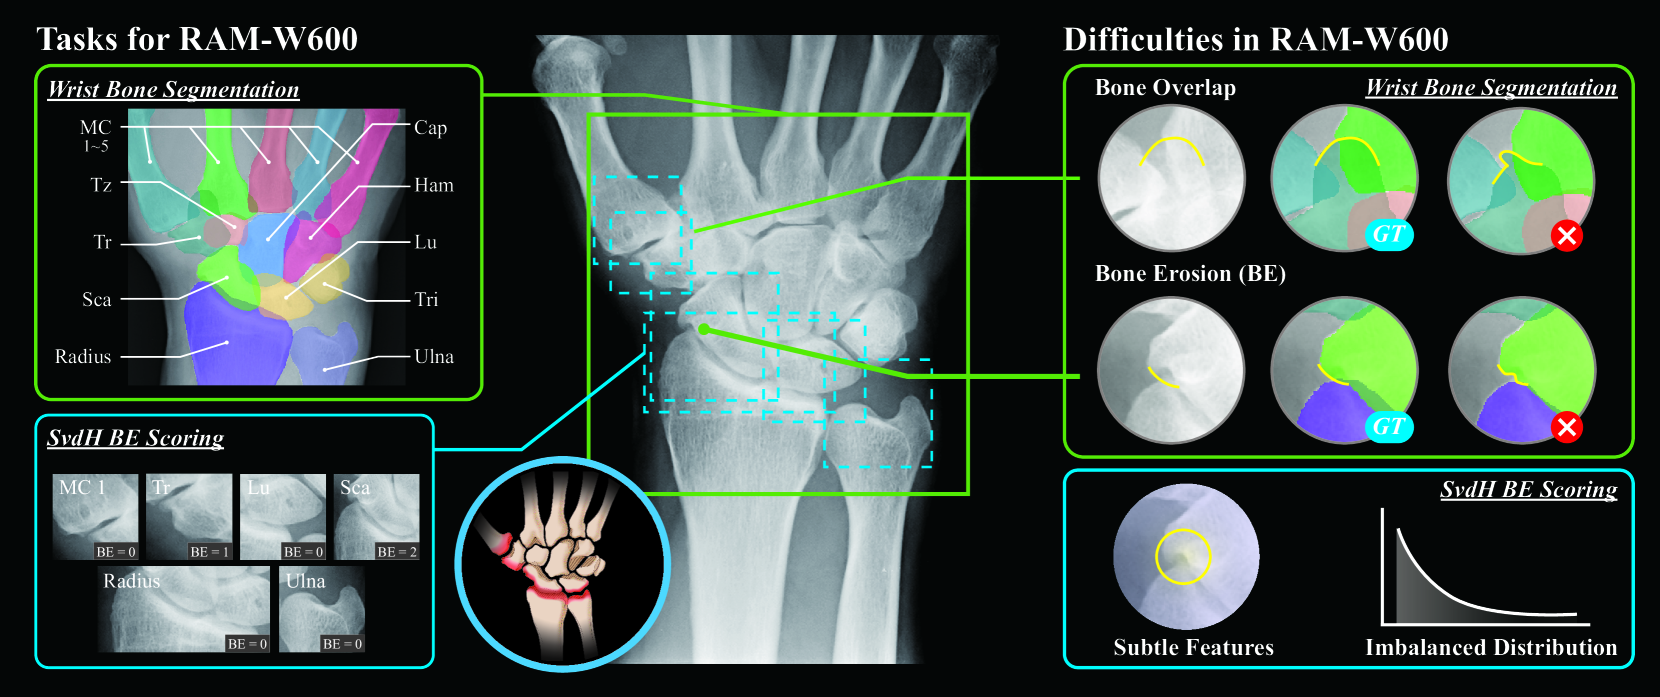

Refer to caption

Figure 1: Overview of the RAM-W600 dataset, designed for wrist bone segmentation and SvdH BE scoring tasks. (MC 1 to 5: Metacarpal 1 to 5; Tz: Trapezoid; Tr: Trapezium; Sca: Scaphoid; Radius: DistalRadius; Cap: Capitate; Ham: Hamate; Lu: Lunate; Tri: Pisiform &\&& Triquetrum; Ulna: DistalUlna)

However, the annotation process of a large-scale dataset is highly challenging and labor-intensive due to the anatomical complexity of the wrist and different pathological changes in the wrist bones. As shown in Fig. 1, (i) Obscured edges due to overlapping structures. The wrist, a structurally complex joint system, features tightly interlocked carpal bones bhat2011radiographic . This configuration frequently leads to overlapping phenomena in conventional radiography (CR), which significantly complicates the identification of each bone’s outer edges. (ii) Morphological alterations resulting from pathological conditions. Due to the progression of RA and other pathological changes, BE, JSN, and osteophyte formation can affect certain bones or joints to varying degrees, often leading to substantial alterations in bone morphology taouli2004rheumatoid ; ezzati2022radiographic ; hoving2004comparison . Moreover, these factors may interact in diverse and combinatorial ways, further complicating the consistency and accuracy of annotations.

Sharp/van der Heijde (SvdH) BE scoring van2000read is a widely recognized task in the automated diagnosis of RA. Nevertheless, it remains highly challenging due to difficulties in both annotation and model training. On the annotation side raven2015radiocarpal ; van1999reliability , (i) accurate annotation demands specialized rheumatological expertise, as assessing the severity of BE is inherently complex. (ii) The process is subjective and prone to substantial inter-observer variability, resulting in inconsistent and uncertain ground truth labels. This subjectivity and ambiguity undermine the quality of supervision available for model training. From a training perspective, (i) the task is further complicated by a severe class imbalance, as cases of high-grade erosion are underrepresented in most clinical datasets. (ii) The pathological features of BE are often subtle, highly localized, small in scale, and demonstrating minimal variation across severity levels, thereby posing substantial challenges for automated detection and classification. Collectively, these factors render SvdH BE scoring a challenging task in developing robust and generalizable deep learning models for RA assessment.

We employed specialized imaging processing methodologies to systematically construct wrist joint data. Initially, image cropping techniques were applied to focus on the wrist region, effectively eliminating interference from extraneous anatomical structures. Subsequent annotation procedures were conducted under the guidance of senior radiologists, comprising three principal components:

• Anatomical Structure Annotation: Precise contour delineation was performed for 14 wrist bones, including the first-fifth metacarpals (MC1-5), trapezium (Tr), trapezoid (Tz), scaphoid (Sca), lunate (Lu), capitate (Cap), hamate (Ham), pisiform &\&& triquetrum (Tri), distal radius (Radius), and distal ulna (Ulna). A multi-label annotation strategy was implemented to independently mark each osseous structure.

• Bone Location Annotation: The SvdH BE scoring system focuses on five key joint regions: MC1, Tz, Sca, Lu, Radius, and Ulna. We performed ROI annotations on these areas.

• SvdH BE Scoring Annotation: BE assessment was conducted using the SvdH scoring system, specifically targeting five critical articular groups: MC1, Tz, Sca, Lu, Radius, and Ulna. This systematic evaluation focused on quantifying erosive changes at these predetermined anatomical sites.

B.6 Wrist Bone Segmentation

Wrist bone segmentation from radiographs is a critical prerequisite for downstream tasks such as joint localization, morphological analysis, and BE scoring in RA assessment. As illustrated in Fig. 6, this task involves delineating multiple overlapping and irregularly shaped carpal and metacarpal bones, which often exhibit low contrast and anatomical ambiguity in radiographs. Accurate segmentation enables reliable quantification of structural features and supports automated interpretation in clinical workflows.

Figure 6: Wrist bone segmentation.(A) Original wrist radiograph. (B) Predicted instance segmentation masks. (C) Ground truth annotations. The right panel reports the segmentation performance per bone.

In this task, we annotate 14 distinct wrist bones, including both carpal, metacarpal components and Radius &\&& Ulna. Notably, the pisiform and triquetrum bones are difficult to distinguish in clinical practice due to their overlapping appearance and low visibility on standard radiographs. Consequently, it is challenging to evaluate them as independent diagnostic regions [45]. Therefore, we merge these two structures into a single category during annotation to reflect their practical indistinguishability. The input to the segmentation model is the wrist ROI cropped from the radiograph, and the output and ground truth are a pixel-wise mask for each annotated bone, as illustrated in Fig. 7.

Figure 7: Image input and annotation.(A) Raw wrist radiograph. (B) Instance bone segmentation mask annotation (C) bone location annotations for target regions. (D) SvdH BE scores assigned to each joint region.

B.7 Classification of BE

BE classification is a key component of the SvdH scoring system, widely adopted in clinical practice for evaluating joint damage in RA. As illustrated in Fig. 8, this task involves identifying subtle pathological changes in individual carpal bones from radiographs, such as cortical breaks and irregular bone surfaces. The classification task is particularly challenging due to the subtlety of erosion features and the high degree of anatomical overlap in wrist joints. Accurate BE detection is essential for automated RA scoring systems and downstream severity assessment, yet remains difficult for both traditional and deep learning models, especially under class imbalance and in early-stage lesions.